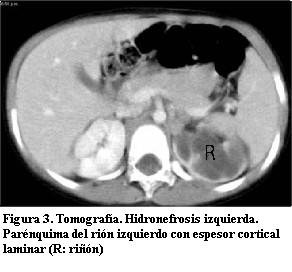

Marcada uréterohidronefrosis izquierda; el parénquima del riñón izquierdo presenta escaso espesor y las cavidades pielocaliciales dilatadas (figuras 3, 4 y 5), con uréter tortuoso en todos sus sectores (figura 6), el cual se afina abruptamente en el sector prevesical inmediato. En el uréter no se observa litiasis de alta densidad, ni compresiones extrínsecas. Riñón derecho sin alteraciones. La vejiga no presenta alteraciones en la pared ni en el contenido. No hay adenomegalias en los territorios estudiados. Hígado, bazo y páncreas sin particularidades. No hay ascitis.